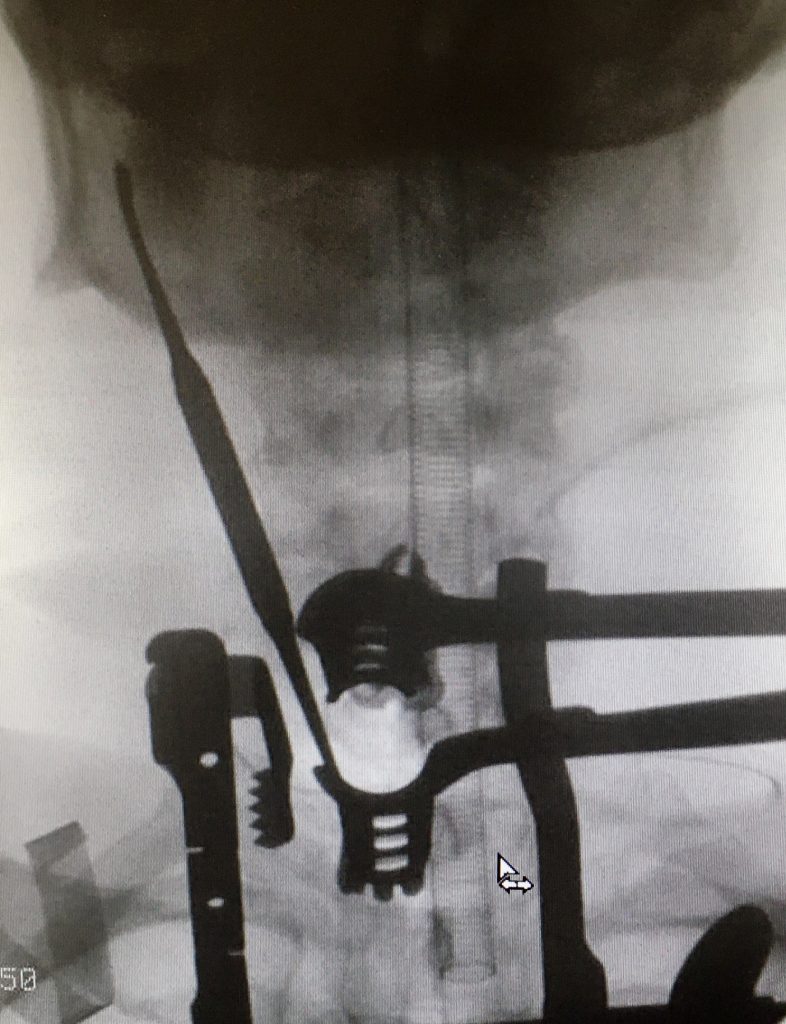

En caso de realizar una fusión, se colocan como implantes una caja de soporte entre las vértebras, rellena de injerto óseo propio y se fijan las vértebras utilizando una placa atornillada. Así logramos el doble objetivo de descomprimir la raíz nerviosa y mantener la estabilidad vertebral.

Cuando la indicación por el contrario es la de realizar una artroplastia discal, el implante que se utiliza es una prótesis de disco anclada a las vértebras.